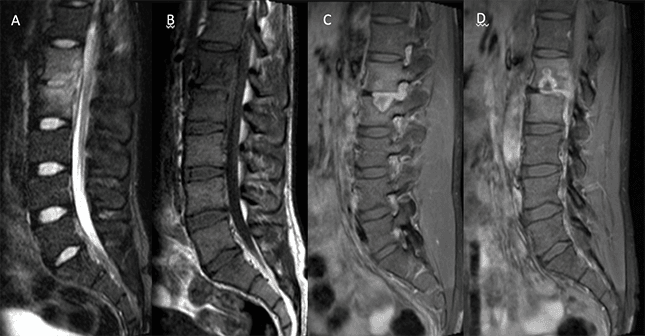

Figura 3.